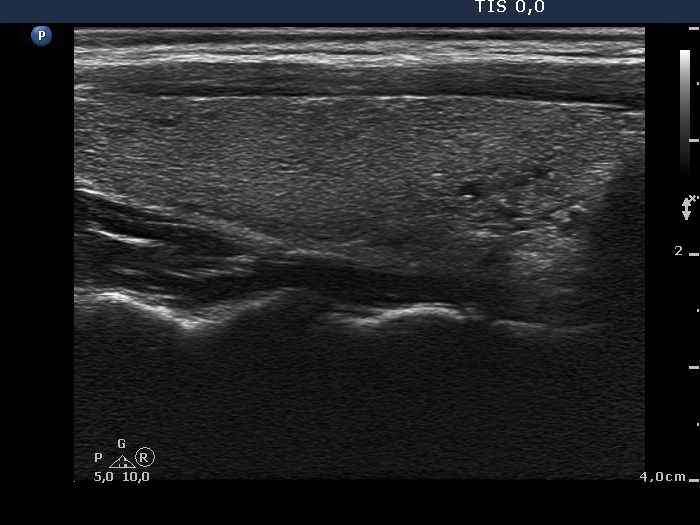

Ultrasonography: The thyroid was echonormal. There was a moderately hypoechogenic inhomogeneous nodule in the lower pole of the right lobe. There were two lymph nodes next to each other above the right thyroid in the submandibular area. The lymph nodes presented a regular hilum.

Cytology was performed from the nodule in the right thyroid and resulted in a benign colloid goiter.

It is edifying to analyze the hyperechogenic figures in the thyroid lesion. While examining the patient, I interpreted these as microcalcifications. However, by preparing the case study I had to regroup these figures. These are in fact presentations of connective tissue and colloid crystals. (See the footnotes of the relevant images.)